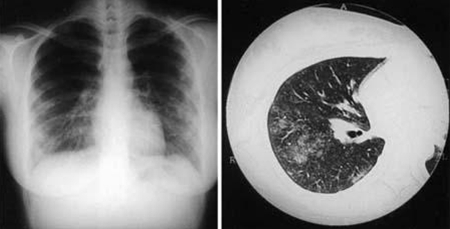

CXR

This may be required in both acute and persistent focalised infection, if there is suspicion of pulmonary complications.

Findings may range from normal to multiple non-specific (without apparent pattern or distribution) opacities of both lungs most consistent with an atypical pneumonia. The most common abnormalities on chest radiography are segmental or lobar opacities. The hallmark of Q fever pneumonia is a finding of several rounded opacities, but this is uncommon.[37]

Pleural effusion, atelectasis, and hilar adenopathy may also be seen, but are rare.

In the context of persistent focalised infection, CXR may identify two different persistent focalised infections: interstitial fibrosis and lung pseudotumour.[Figure caption and citation for the preceding image starts]: Coxiella burnetii pneumonia. CXR and CT scan from a 21-year-old woman with Coxiella burnetii pneumonia; CXR shows multiple areas of soft consolidation in the middle-to-lower lung fields bilaterally; CT scan shows poorly defined centrilobular nodules and air space consolidationOkimoto N, et al. Respirology. 2004;9:278-282; used with permission of John Wiley & Sons Ltd [Citation ends].

chest CT

Typically, this is not routinely required but may be used to evaluate pulmonary complications in acute disease.[Figure caption and citation for the preceding image starts]: Coxiella burnetii pneumonia. CXR and CT scan from a 21-year-old woman with Coxiella burnetii pneumonia; CXR shows multiple areas of soft consolidation in the middle-to-lower lung fields bilaterally; CT scan shows poorly defined centrilobular nodules and air space consolidationOkimoto N, et al. Respirology. 2004;9:278-282; used with permission of John Wiley & Sons Ltd [Citation ends].